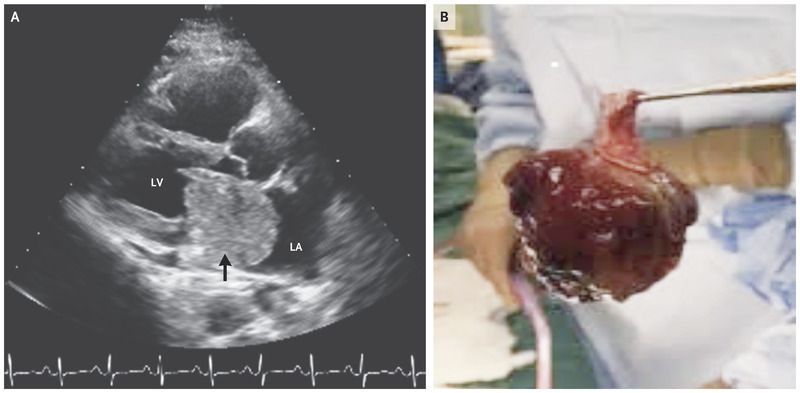

A previously healthy 47-year-old woman presented to her primary care physician with a 6-month history of worsening exertional dyspnea, progressive fatigue, and orthopnea. The physical examination was notable for sinus tachycardia, an abnormal heart sound initially thought to be an S3 gallop, and edema of both legs. A chest radiograph showed pulmonary venous congestion. Transthoracic echocardiography revealed a mass that was attached to the interatrial septum, with partial prolapse into the left ventricle obstructing the mitral-valve inflow during diastole (Panel A, arrow [LA denotes left atrium, and LV left ventricle],. The additional heart sound after the S2 was recognized as a characteristic “tumor plop.” The patient underwent excision of the left atrial mass (which measured 5.7 cm by 4.3 cm by 5.0 cm) (Panel B), resection of the interatrial septum, and reconstruction with a bovine pericardial patch. Pathological analysis confirmed the diagnosis of an atrial myxoma. Cardiac myxomas are the most common type of primary cardiac tumor in adults and usually occur in the left atrium. If the condition goes untreated, complications such as congestive heart failure, embolic stroke, and sudden death can occur. Surgical resection is the indicated therapy. A postoperative echocardiogram showed a normal ejection fraction and no flow across the interatrial septum. The patient had an unremarkable postoperative course and was discharged home.